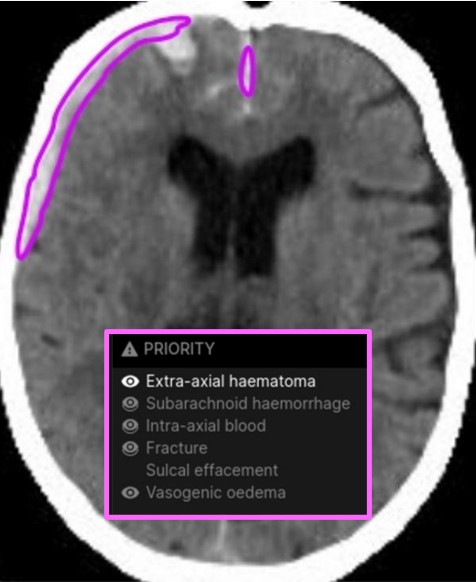

Harrison Brain CT reports acute and chronic cranial processes in CT scans using tables and direct annotation in CT images.

The comprehensive detection of cranial pathologies is one of the main tasks of neurologists and radiologists, be it in acute medicine or in routine diagnostics. Harrison Brain CT assists with the depiction of 130 pathologies.

Non-enhanced cranial CT of a 58-year-old patient after a skiing accident. Harrison Brain CT detects acute multicompartmental hemorrhages, fracture (not shown), lists the results and annotates them directly in the CT images.